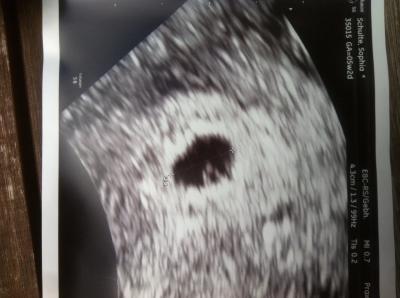

Huhu ihr Lieben, wollte doch auch mal eben berichten, dass ich heute morgen beim Fa war. Bin nun 5+2, man hat eine Fruchthöhle gesehen und einen 7mm Krümmel :-) Nun heißt es vier lange Wochen abwarten und hoffen, dass das Herzchen bald schlägt! Anbei das erste Bild von meinem Krümmelchen :-) Muss mich noch sooo zusammen reißen es nicht meiner Tochter zu erzählen. Schick euch liebe Grüße, Sophia

Bild zu Fa- Termin, nun heißt es abwarten... - Forum für März - Mamis

genau so hat es gestern bei mir , bei genau 5+2 auch ausgesehen ich darf in 2 Wochen wieder kommen Alles Gute Dir weiterhin